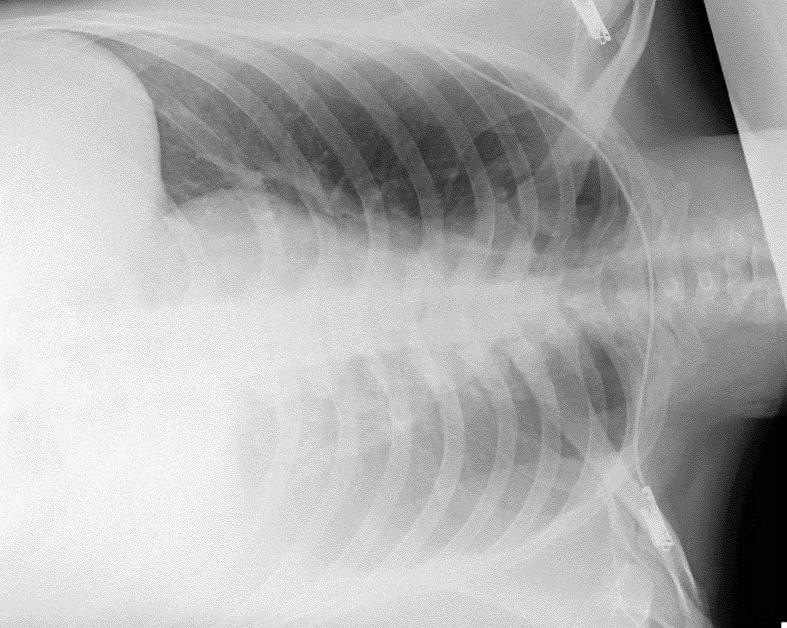

dam-vao-nguc2-4541.jpg

Kết quả chụp X-quang của bệnh nhân bị đâm vào ngực bằng vật sắc nhọn. Ảnh: BVCC